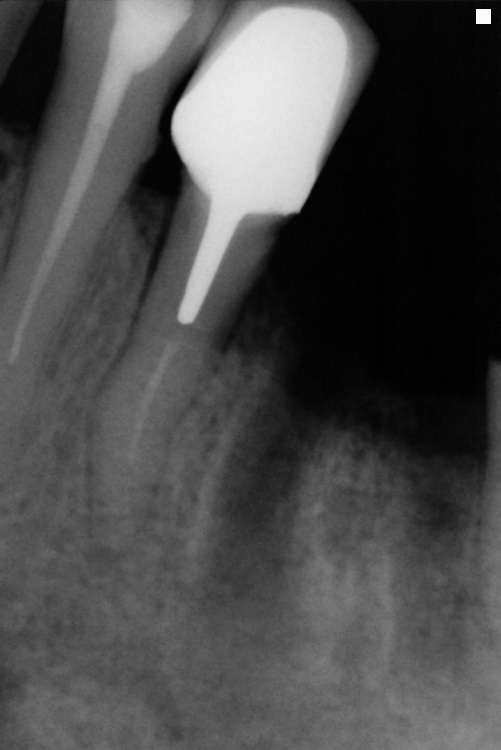

IO000001.jpg

2020-07-28 13:58 70K